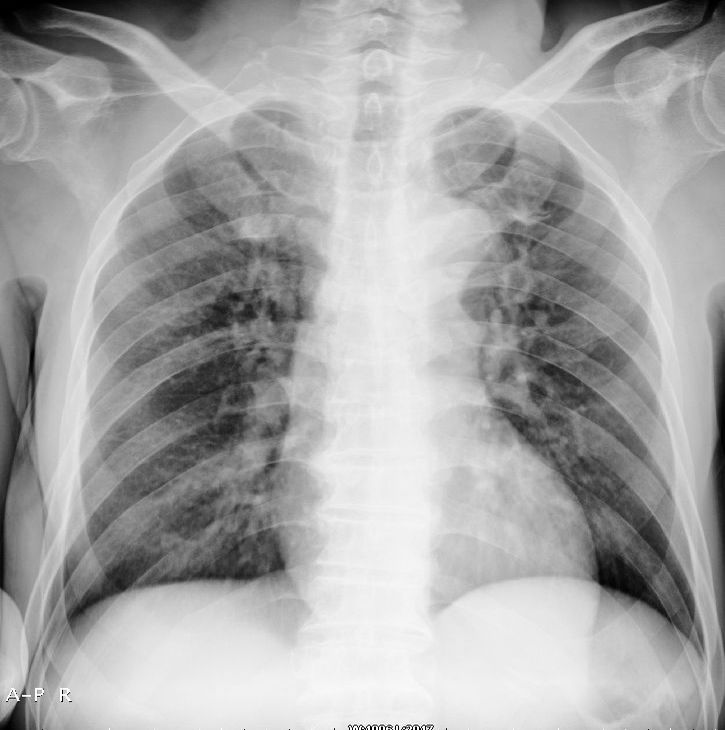

以下是一周前外伤时的dr:

一周前胸片无异常,不考虑肿瘤,现x片及ct表现应与外伤有关,考虑左侧外伤性膈疝,并左下肺不张。右肺挫裂伤。少量胸水。

一周前胸片无异常,不考虑肿瘤,现x片及ct表现应与外伤有关,考虑左侧外伤性膈疝,并左下肺不张。右肺挫裂伤。少量胸水。支持

右侧第7肋骨腋段骨折并右肺挫伤;左侧膈疝并肺不张。